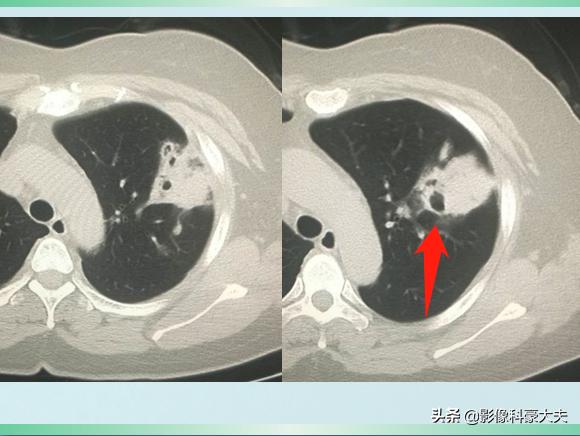

我们先不公布答案,继续看她治疗10天后的复查CT:

对比前两次片子,黑色空洞影变得更大了,周围的白色炎症斑片影吸收好转了。

这是一种什么细菌呢?为什么会短时间引起肺组织坏死空洞?经过实验室培养,医生们找到了真相——肺炎克雷伯杆菌。